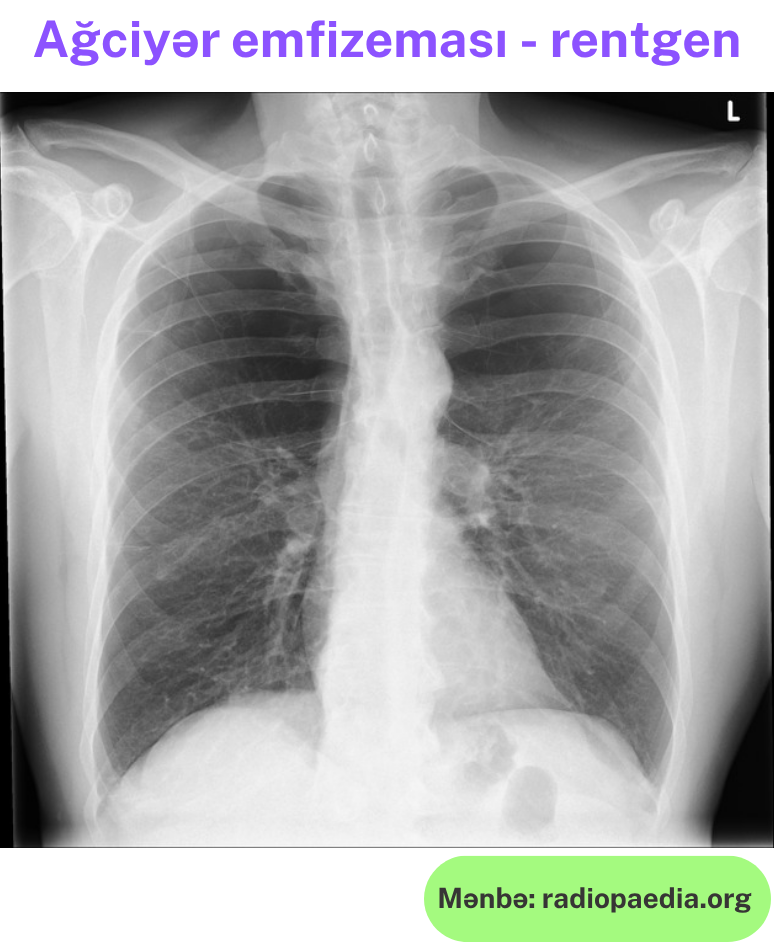

Rentgen müayinəsi:

- Döş qəfəsinin genişlənməsi

- Diafraqmanın aşağı enməsi və düzləşməsi

- Ağciyərdə havalanmanın artması